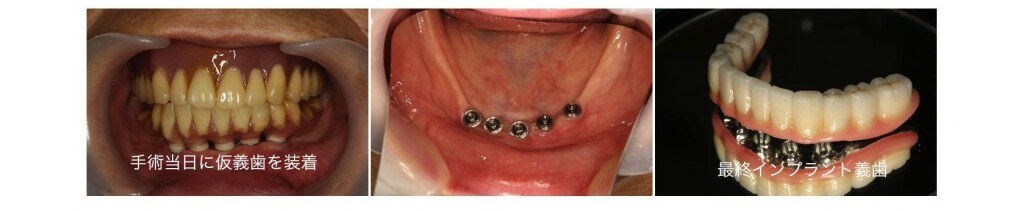

下顎の著しい骨吸収を伴う無歯顎症例です。下顎の顎堤は吸収し義歯の安定が望めない状態です。こうした場合には顎堤の前方部分に複数のインプラントを埋入し連結する事で大臼歯部までの歯列を完成させる事が可能となります。

手術当日に仮義歯を固定する事でその日から安定した咬み合わせを手に入れる事ができました。